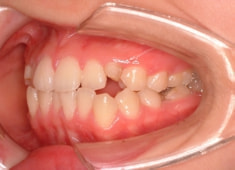

治療前